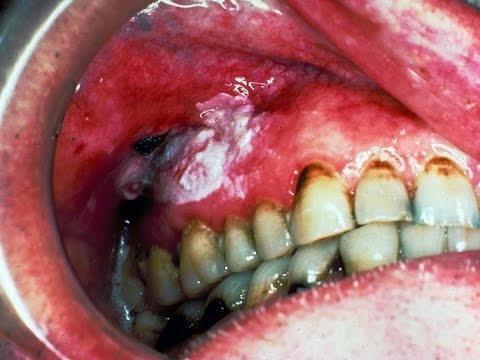

حذرت جامعة جازان من انتشار مرض سرطان الفم مؤكدة أن ثلث الحالات المرضية في المملكة يعود إلى منطقة جازان.

وقالت جامعة جازان في تغريدة لها عبر حسابها على تويتر: هل تعلم: أن ثلث حالات سرطان الفم بالمملكة تم تشخيصها بمنطقة جازان، حيث بلغت النسبة 35 ٪ ، من الحالات المشخصة.

وأوضحت الجامعة أن أكثر مسببات الإصابة بسرطان الفم هي ” الشمة ”

والمعروف أن الشمة هي نبتة تجفف وتطحن وتكون على شكل مسحوق أصفر مائل إلى الخضار يحتوي على التبغ المخلوط بمادة بلورية بيضاء وينتشر استعمالها عن طريق المضغ في بعض البلاد العربية وكذلك في أميركا والسويد.

والشمة مشهورة بقذارتها ورائحتها النافذة الكريهة، وتستعمل بوضعها في تجويف الفم أو بين الشفة السفلي واللثة بهدف استحلاب المادة الفعالة فيها وهي النيكوتين، ويساعد على امتصاص هذه المادة من أغشية الفم وجود مادة قلوية ومسحوق وكربونات الصودا المائية، حيث إن مسحوق الشمة يستعمل دون تدخين.

وتعد إصابات الفم من أخطر ما ينجم عن استعمال الشمة، حيث تسبب تغييراً في لون الأغشية المخاطية المبطنة للفم من حدوث إصابات تعتبر نذيراً للإصابة بسرطان الفم.